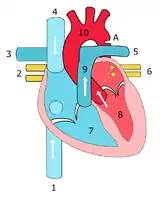

Illustration showing a heart with a coarctation of the aorta

Illustration showing a heart with a coarctation of the aorta Sketch showing heart with coarctation of the aorta. A: Coarctation (narrowing) of the aorta. 1:Inferior vena cava, 2:Right pulmonary veins, 3: Right pulmonary artery, 4:Superior vena cava, 5:Left pulmonary artery, 6:Left pulmonary veins, 7:Right ventricle, 8:Left ventricle, 9:Pulmonary artery, 10:Aorta

Sketch showing heart with coarctation of the aorta. A: Coarctation (narrowing) of the aorta. 1:Inferior vena cava, 2:Right pulmonary veins, 3: Right pulmonary artery, 4:Superior vena cava, 5:Left pulmonary artery, 6:Left pulmonary veins, 7:Right ventricle, 8:Left ventricle, 9:Pulmonary artery, 10:Aorta Schematic drawing of alternative locations of a coarctation of the aorta, relative to the ductus arteriosus. A: Ductal coarctation, B: Preductal coarctation, C: Postductal coarctation. 1: Aorta ascendens, 2: Arteria pulmonalis, 3: Ductus arteriosus, 4: Aorta descendens, 5: Truncus brachiocephalicus, 6: Arteria carotis communis sinistra, 7: Arteria subclavia sinistra